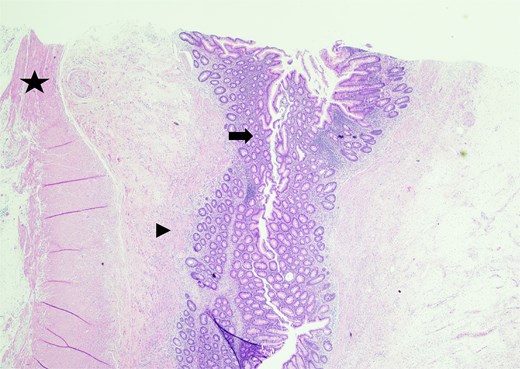

Sectioning of the intact vermiform appendix, top portion, showing the muscularis propria (star), muscularis mucosa (arrowhead), and colonic mucosa (arrow).

In the operating room, multiple adhesions from the patient’s prior colostomy site and colon resection were noted. The appendix was found to be dilated, acutely inflamed, and hyperemic, consistent with the suspected diagnosis of acute appendicitis. Adhesions from the appendix to the abdominal sidewall were dissected bluntly, pulling the appendix to a more medial position. The harmonic surgical device was used to divide the appendix mesentery and the gastrointestinal anastomosis (GIA) stapler with a blue load was used to divide the appendix from the base of the cecum. Final pathology showed an intact vermiform appendix measuring 6.5 × 1.5 cm with 3.2 × 2.5 × 1.6 cm portion of the attached mesoappendix. On gross examination, tan-pink hemorrhagic serosa with minimal adhesions and no exudate was noted. Sectioning of the specimen revealed a 0.5-cm in diameter lumen filled with a moderate amount of hemorrhagic purulent fecal material and at the distal tip, an intact diverticulum with wall measurement up to 0.2 cm in average thickness (Figs 1 and 2).